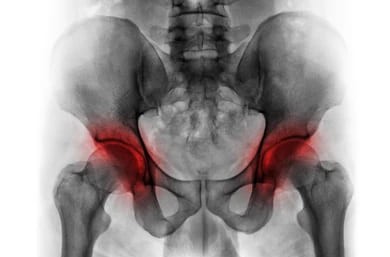

골반 건강에 대해 많이들 걱정하고 계시죠? 특히 골반괴사라는 질병을 예방하거나 이미 앓고 있는 분들이 많습니다. 오늘 은 골반괴사에 좋은 음식 정리했습니다. 요즘 건강 관리가 중요하다는 얘기를 많이 듣지만, 사실 중요한 건 무조건 약에만 의존하지 않고, 우리가 먹는 음식부터 챙기는 것이 중요하다고 생각합니다. 이글에서는 여러분께 골반괴사에 도움이 되는 음식들은 어떤 것들이 있는지, 그리고 뼈건강에 좋은 영양소에 대해 자세히 설명해 드리겠습니다.

골반괴사는 골반 주위의 뼈가 혈액 공급을 충분히 받지 못해 괴사 하는 질병입니다. 이로 인해 뼈가 약화되고 통증이 동반됩니다. 이때 음식은 어떻게 골반괴사 예방과 치료에 도움이 될까요? 뼈 건강을 유지하는 데 필수적인 영양소를 음식으로 섭취함으로써 골반괴사를 예방하거나 증상을 완화할 수 있습니다. 칼슘, 비타민 D, 마그네슘 등 뼈 건강에 좋은 영양소를 충분히 섭취하는 것이 중요합니다. 이러한 영양소는 음식으로 쉽게 얻을 수 있어서 약에 의존하지 않고도 건강을 관리 수 있습니다.